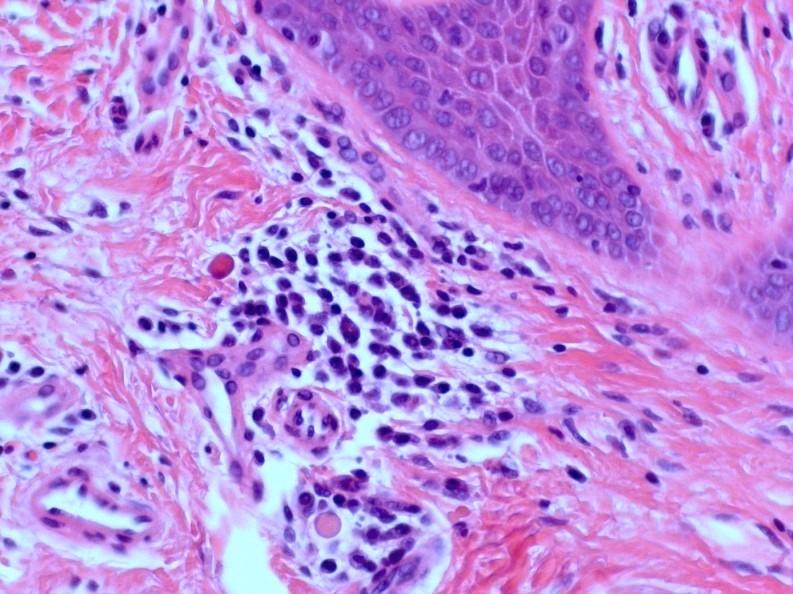

Adenoid cystic carcinoma

 Wide age range

 Slow growing with tendency for perineural spread

 Tubular, cribriform and solid patterns

 2 cell populations: ductal cells and abluminal myoepithelial cells

 Cytologically bland, angular and dense chromatin

 Cribriform pattern: multiple punched out holes “pseudocysts”

 Contain dense eosinophilic basement membrane-like material or bluish mucopolysaccharides

 Perineural invasion +++

 5 yr survival good, 20 yrs <10%

 Lung metastases seen later in course